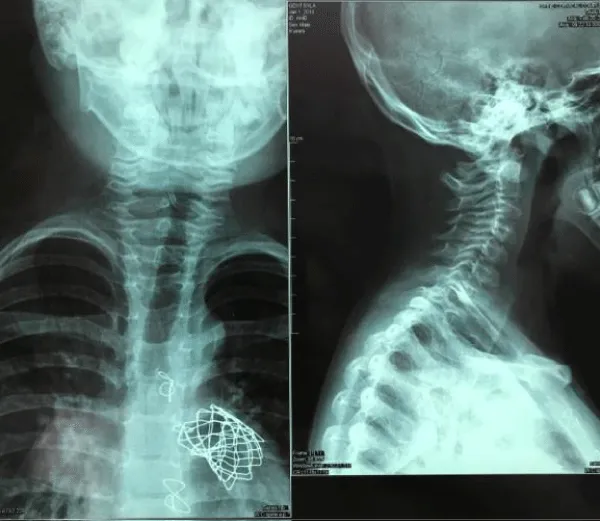

A 5-day-old male infant, with initials GS, from the fourth and normal controlled pregnancy, weighing 3520g, from both healthy parents, was transferred from regional hospital at our centre as a reason of central cyanosis and important heart murmur. Delivery was normal, with normal Apgar score and despite being ventilated on 100% oxygen, pulse oximetry could not be raised above 88%. Objectively a short, webbed neck and a low hairline and suspicion were for Klippel-Feil syndrome. A complete history and careful physical examination was obtained including X-ray chest and transthoracic echocardiography examination. Echocardiography presented severe form of tetralogy of Fallot. Anteroposterior (AP) and lateral radiographs of the cervical spine was done which presented abnormal development of C1, C2 and C3 vertebra with massive fusion of the cervical spine. At age of four month for surgical intervention in Linz, Austria was sent, where complete correction of tetarlogy of Fallot was done. Genetic testing confirmed new mutations in the GDF6 gene. At age of 7 years as a consequence of huge pulmonary insufficiency Melody valve was implanted at the same centre. Actual medical status is well, within normal school and other physical activities (Figure 6).

Download Image

Figure 6: Case 5. X-ray images shows occipito-cervical junction.Note Melody valve implanted as a consequence of pulmonary insufficiency after complete TOF repair.